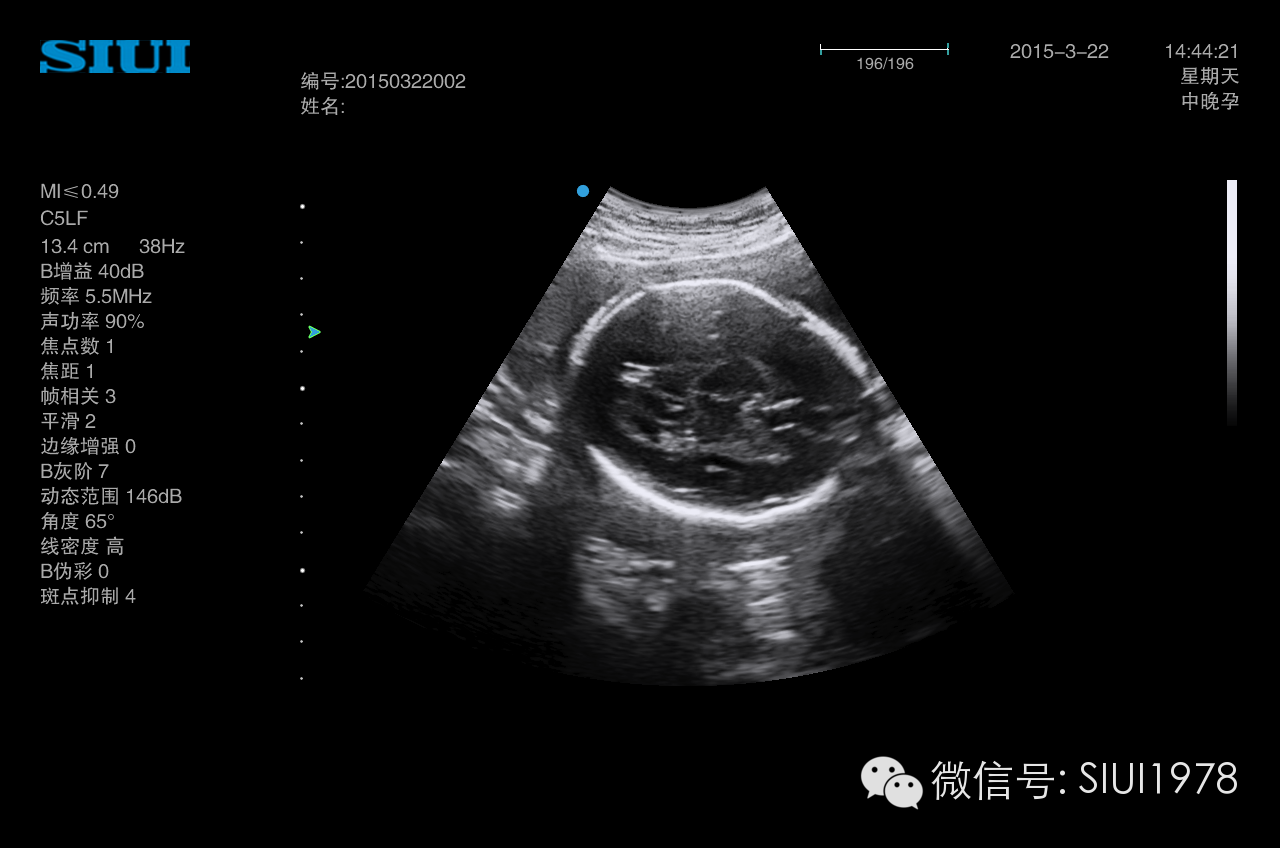

中孕期胎儿超声检查规范图诊断图片,b超教学图解图谱

胎儿超声标准切面详解

胎儿脑部超声切面图解

胎儿颅脑超声解剖图

胎儿颅内结构超声切面